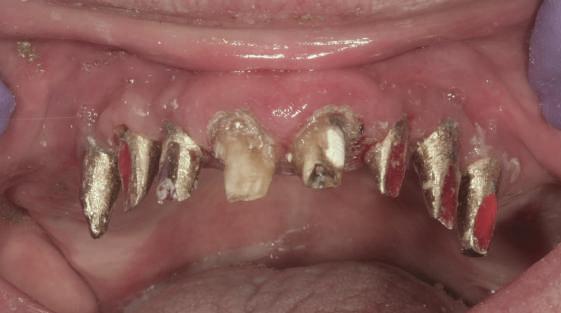

Reprepararea intraorală a bonturilor Acest pacient prezenta dentiţia maxilară compromisă, refuzând proteza mobilizabilă. Prin abordarea în etape, se menţin o parte din bonturile dentare naturale; s-a observat recesie în momentul amprentării pentru cel de-al doilea grup de implanturi.

Fig. 1 prezintă pacientul după inserarea primului set de bonturi implantare individualizate; dinţii naturali adiacenţi

sunt încă prezenţi pentru a susţine puntea provizorie.

Şapte luni mai târziu (fig. 2), acele bonturi individualizate din prima etapă au manifestat semne de recesie de 1-3mm. Atitudine: S-a decis reprepararea intraorală a tuturor bonturilor (fig. 3), astfel încât toate marginile bonturilor să fie la nivelul sau sub marginea gingivală (de notat că 1.1. şi 2.1. au fost submersaţi ulterior pentru a avea sprijin implantar deplin).

Deşi reprepararea a îmbunătăţit marcat estetica finală, a necesitat aplicarea şnurului de retracţie, amprente noi şi turnări noi.

Un caz separat dar similar ilustrează în figurile 4 și 5 reprepararea intraorală a bontului.

Cazul (1): Reprepararea intraorală a bonturilor Figurile

1. Aspect după inserarea primului set de bonturi implantare individualizate.

2. După 7 luni, bonturile individualizate din prima etapă au prezentat recesie de 1-3mm.

3. Bonturile repreparate intraoral.

Alt caz (1) Figurile

4. După osteointegrarea implantului 2.4., s-a observat recesia în etapa de amprentare a implantului 2.5.; s-a decis reprepararea marginilor bontului individualizat CAD/CAM 2.4. Înainte de preparare s-a aplicat şnur de retracţie pentru a evita lezarea ţesutului şi a îmbunătăţi vizibilitatea dintelui 2.3. şi a marginii bontului implantar individualizat. Aşa cum era de aşteptat, recesia a fost mai mare de-a lungul versantului distal al bontului 2.4. adiacent locului de extracţie vindecat/cu implantul mai nou.

5. Bontul individualizat aplicat (2.5.) cu bontul repreparat anterior (2.4.). Nu a survenit recesie nouă de o perioadă de peste 3 ani.